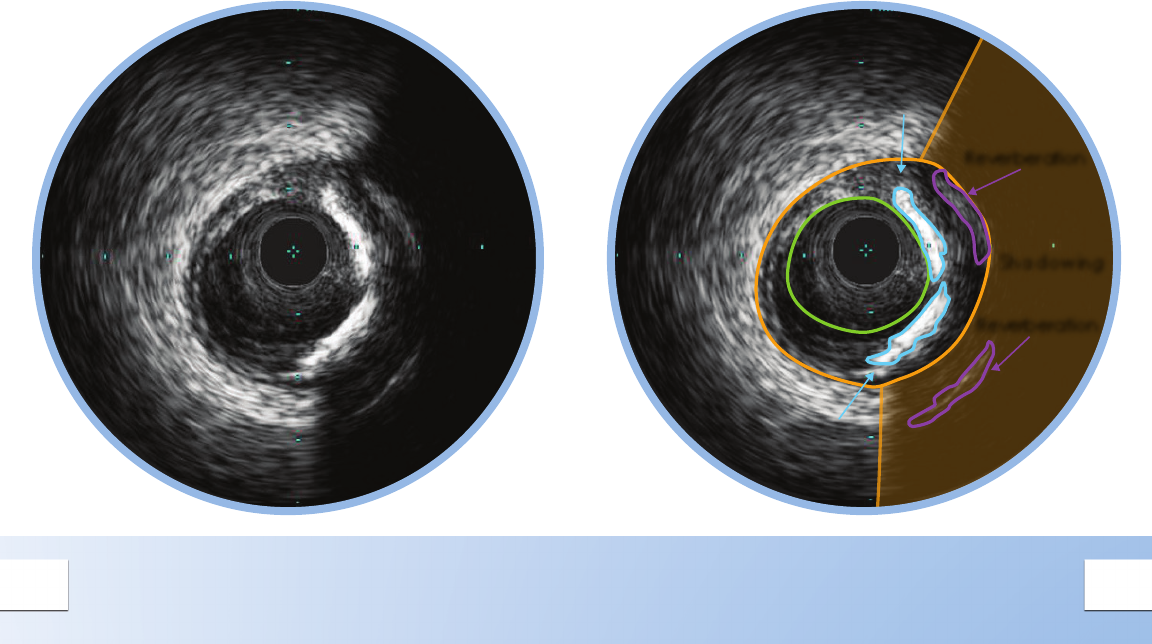

PLAQUE WITH CALCIUM

There are two large bands of calcium in this plaque

with acoustic shadowing arcs behind them.

Calcium is indicated by very bright areas with acoustic

shadowing that blocks out the image behind it.

Reverberations may also been seen. This shadowing

occurs because the high density of calcium prevents the

ultrasound from passing through.

Detection of calcium is a critical factor in

determining the optimal PCI strategy.

Study data comparing IVUS and angiographic

based assessments of calcium reported that IVUS

detected calcium signicantly more often.*